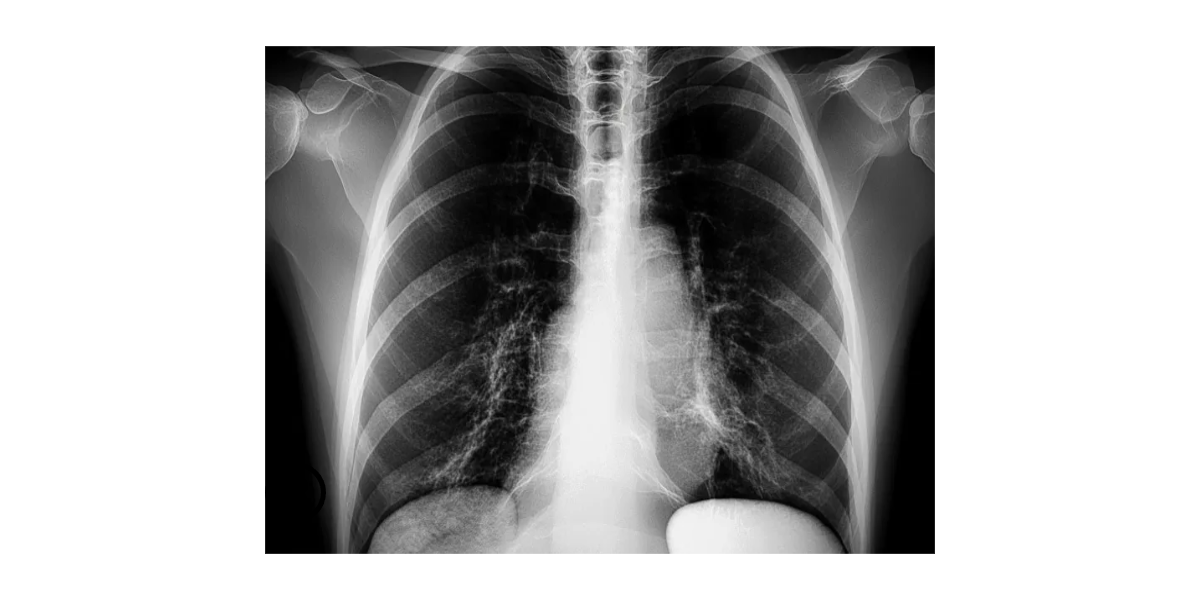

폐렴이 의심되면 조기에 의료기관을 방문해 정확한 검사와 진단을 받는 것이 중요하다. 진단에는 흉부 엑스선 촬영, 혈액 검사, 혈액 배양, 객담 검사 등이 포함되며, 필요시 추가적인 영상 검사나 특수 검사가 이루어진다. 원인 병원체를 파악하면 보다 적절한 약물 치료를 선택할 수 있다. 세균성 폐렴의 경우 항생제가 중심 치료가 된다. 노년층에서는 간 및 신장 기능을 고려하여 용량과 약제를 신중히 결정해야 하며, 기존 복용 중인 약물과의 상호작용을 확인해야 한다. 항바이러스제는 특정 바이러스가 원인일 때 사용되며, 항진균제는 드물지만 진균 감염이 원인인 경우 투여된다. 치료 시작 후 증상 개선 여부를 면밀히 관찰하고, 48~72시간 내에 호전이 없으면 치료 계획을 재검토해야 한다. 산소 치료는 저산소증을 개선하기 위해 필요할 수 있다. 중증인 경우에는 입원하여 집중적인 모니터링과 치료를 받는 것이 안전하다. 탈수나 전해질 불균형이 동반되면 정맥로를 통한 수액 보충이 필요하며, 기침과 가래 배출을 돕기 위한 물리치료나 호흡 재활도 회복에 도움이 된다. 중환자 치료가 필요한 경우 기계환기 치료를 시행하기도 한다. 항생제 치료 기간은 병의 중증도와 환자의 면역 상태에 따라 달라지며, 일반적으로 최소 며칠 이상을 권장하지만 노년층에서는 더 길게 유지될 수 있다. 치료가 끝난 후에도 완전한 회복을 위해 추가적인 평가와 재활이 필요하다. 폐 기능 저하가 의심되면 폐기능 검사와 영상 검사를 통해 후유증 여부를 확인하고 적절한 폐재활 프로그램을 권장할 수 있다. 재발 방지를 위해서는 기저 질환의 철저한 관리가 필수적이다. 당뇨나 심부전, 만성 폐쇄성 폐질환 같은 만성 질환을 가진 환자는 해당 질환을 잘 조절함으로써 폐렴 발생 위험을 낮출 수 있다. 가족과 돌봄 제공자는 초기 증상을 주의 깊게 관찰하고 이상 징후가 보이면 즉시 의료진과 상담해야 한다.